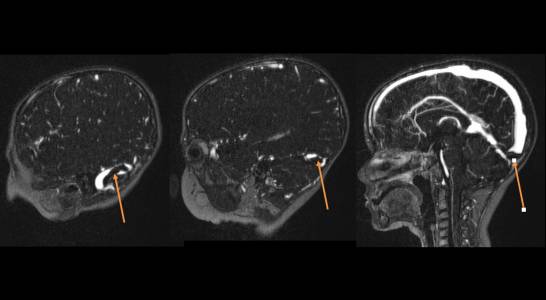

Paciente atendido na emergência com quadro de diarreia de início a 48h. Durante realização de hemograma foi flagrada a presença de células imaturas no exame, sendo então encaminhado para o tratamento com a oncopediatria. Realizou mielograma que diagnosticou leucemia linfoide aguda. Foi então submetido a tratamento intratecal com quimioterápicos. Com 48 horas paciente evoluiu com rebaixamento do nível de consciência. Sendo diagnosticada trombose venosa cerebral (TVC).

Paciente foi avaliado e indicado tratamento com anticoagulação utilizando enoxaparina em dose plena. O paciente apresentou piora progressiva dos sintomas, chegando a apresentar hemiplegia a esquerda. Nova ressonância é solicitada demonstrando piora da trombose.